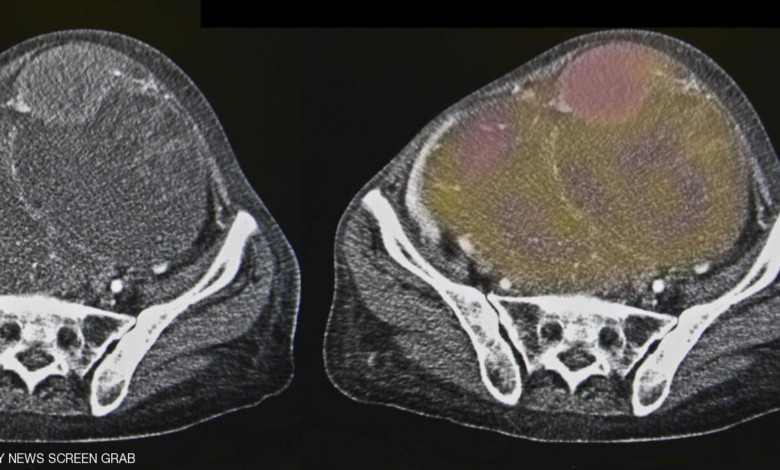

وخلال التجارب، استطاع عقار أونكس-0801 تقليص حجم الأورام في 7 من أصل 15 مريضا خضعوا للتجارب.

ويدخل أونكس-0801 الخلايا السرطانية عن طريق محاكاة حمض الفوليك – جيث أن سرطان المبيض لديه عدد كبير من مستقبلات حمض الفوليك. ثم يقتل الخلايا عن طريق وقف عمل بروتين يسمى سينثاس ثيميديلات.